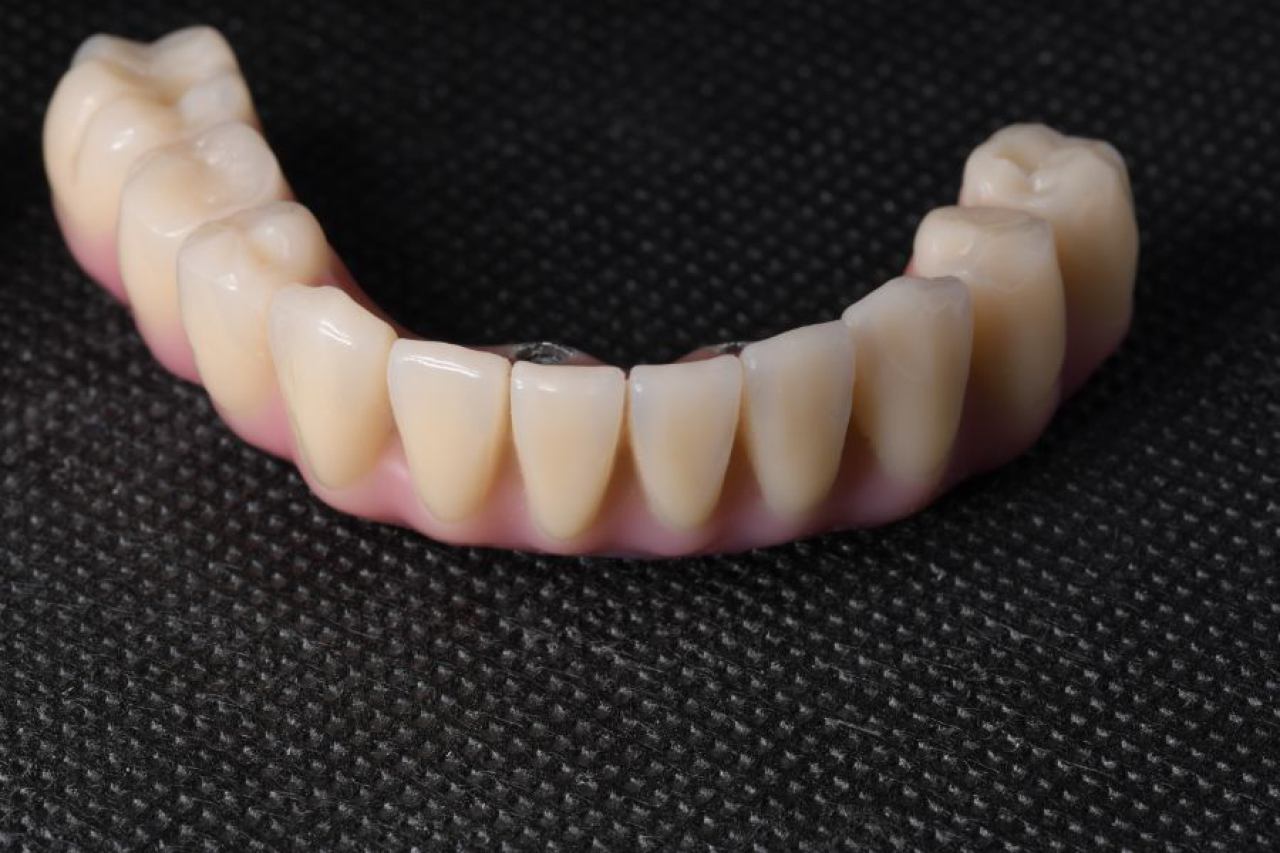

Protetika - mostovi i krunice

Dentalna protetika uključuje fiksne i mobilne radove kojima se nadoknađuje djelomična ili potpuna bezubost. Njihov cilj je povratiti funkciju žvačnog sustava i u konačnici, vrhunsku estetiku.

Marković Dental Clinic u svojoj ponudi ima metalkeramičke radove, potpunokeramičke radove, te u narodu zvane „bezmetalne", odnosno zirkonske radove.